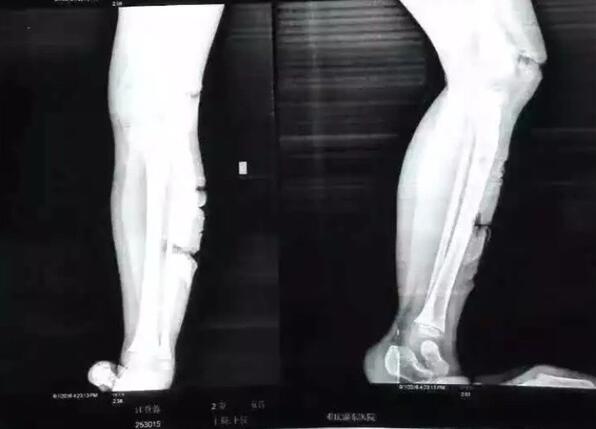

6月1日,重庆奉节县冯坪乡明堂村一名3岁留守女童小容(化名)四肢被人砍伤。 @重庆时报 图 6月1日儿童节,重庆奉节县冯坪乡明堂村一名3岁留守女童小容(化名)的四肢被砍伤,砍伤她的是邻居——8岁男孩江某某。

3岁留守女童小容(化名)四肢被人砍伤。

6月2日,澎湃新闻(www.thepaper.cn)从重庆奉节县公安局证实,江某某系智力三级残疾,目前伤者正在医院接受治疗,暂无生命危险。事发后,当地ZF正积极协调处理善后事宜,并责令江某某的监护人对其严加教育看管。

2日中午,《重庆时报》官方微博@重庆时报 发布消息:昨天(6月1日),奉节冯坪乡,一位年仅3岁的留守儿童被8岁智障儿童连砍20多刀。据了解,两人是表亲,3岁孩子的父母因外出打工,被爷爷送到医院。手术在进行4个小时后,孩子暂无生命危险。